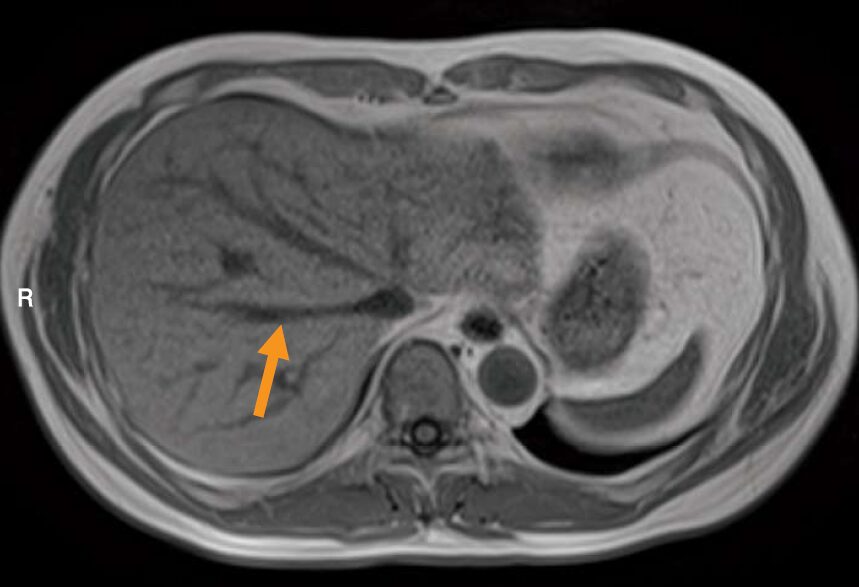

腹部MRIのT₁強調像を示す。矢印で示すのはどれか。

この画像で矢印が示す血管は、枝分かれすることなく、肝臓の後方へ向かってまっすぐ走行しています。これはまさしく、「幹」である肝静脈の典型的な走行です。

3.肝静脈

- ✅ 正解

- 肝後方から直線的に走行し、肝上部で下大静脈へ流入するのが特徴。矢印の血管はこれに一致します

- 矢印が示すのは肝静脈。肝臓の後方から直線的に走行し、下大静脈へ流入するのが特徴。